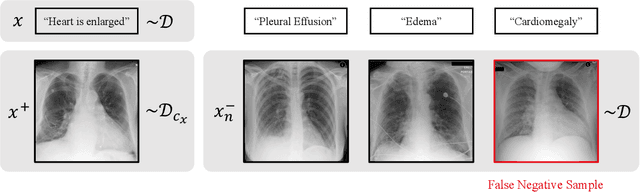

Abstract:Self-supervised representation learning on image-text data facilitates crucial medical applications, such as image classification, visual grounding, and cross-modal retrieval. One common approach involves contrasting semantically similar (positive) and dissimilar (negative) pairs of data points. Drawing negative samples uniformly from the training data set introduces false negatives, i.e., samples that are treated as dissimilar but belong to the same class. In healthcare data, the underlying class distribution is nonuniform, implying that false negatives occur at a highly variable rate. To improve the quality of learned representations, we develop a novel approach that corrects for false negatives. Our method can be viewed as a variant of debiased constrastive learning that uses estimated sample-specific class probabilities. We provide theoretical analysis of the objective function and demonstrate the proposed approach on both image and paired image-text data sets. Our experiments demonstrate empirical advantages of sample-specific debiasing.